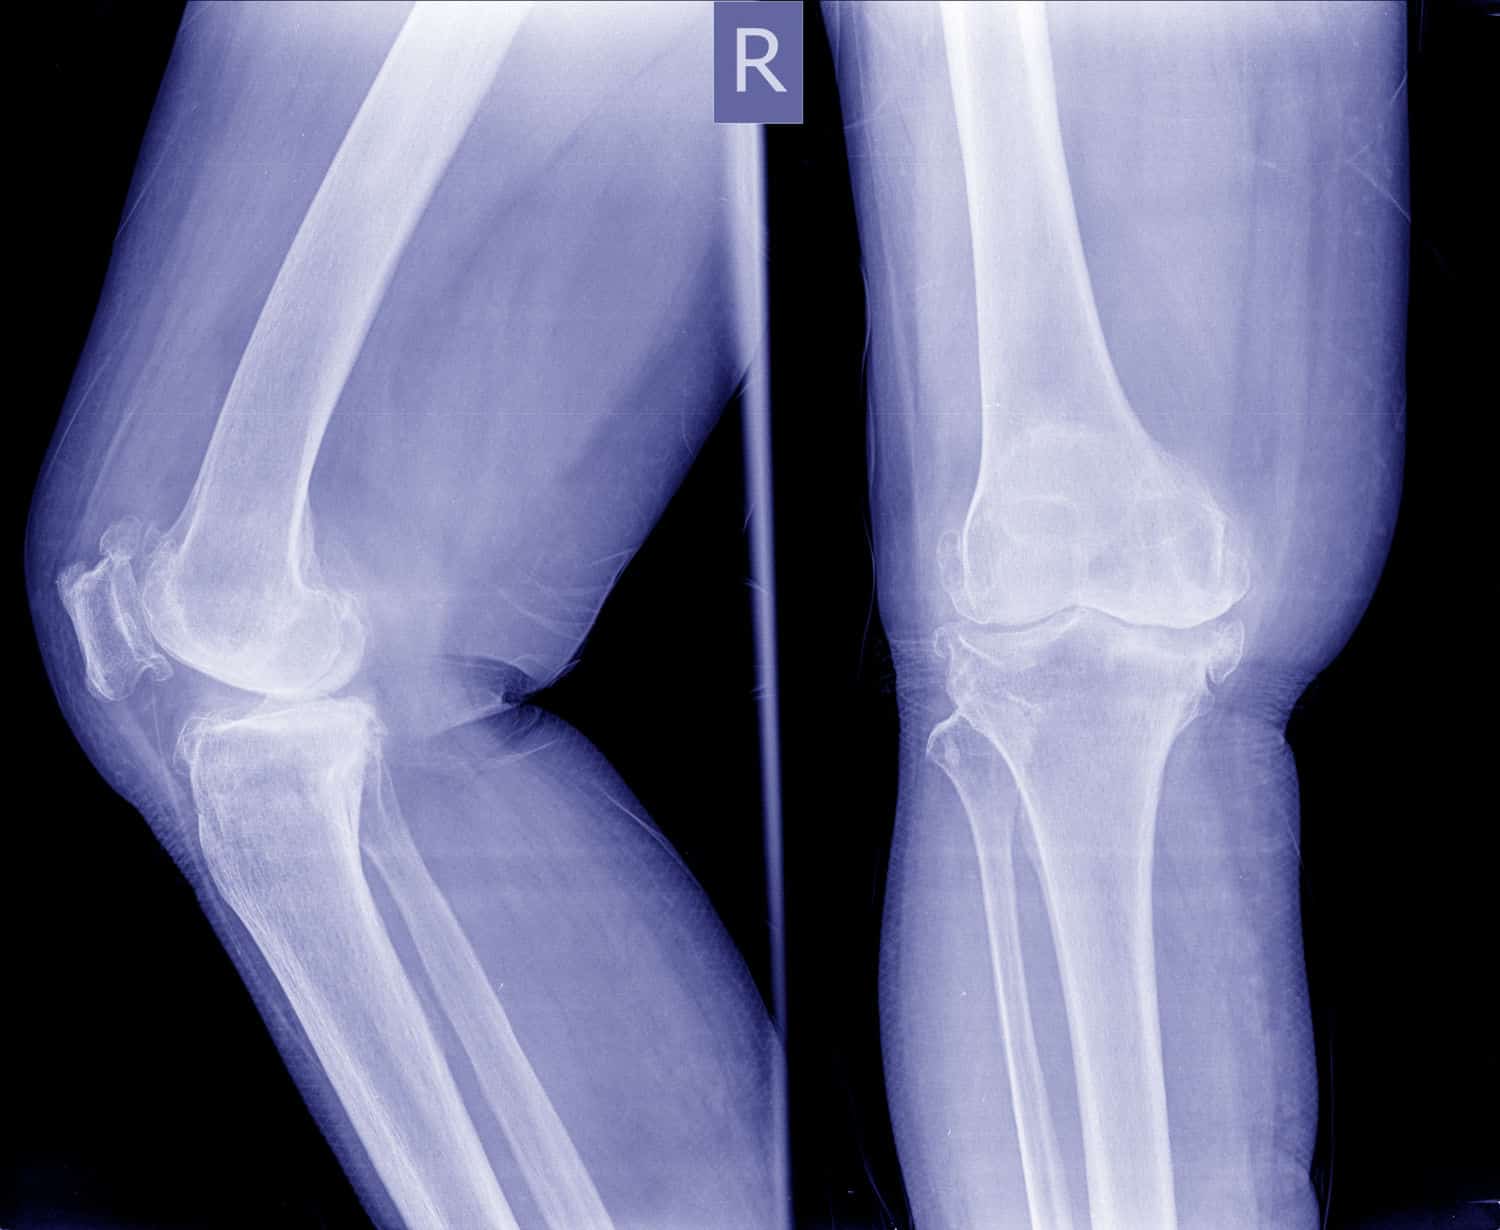

O diagnóstico de osteoartrose do joelho, na maioria dos casos, tem como base o histórico, exames clínicos e radiografias.

A opção da radiografia é o procedimento de imagem mais indicado devido a ser validado, mais acessível e muito disponível. Bem como, suas imagens facilitam realizar a classificação da importância da doença.4

Os aspectos radiológicos da osteoartrose do joelho evidenciam “redução do espaço articular, aumento da densidade óssea subcondral, alterações proliferativas marginais das articulações e formação de cisto no osso subcondral.” 4